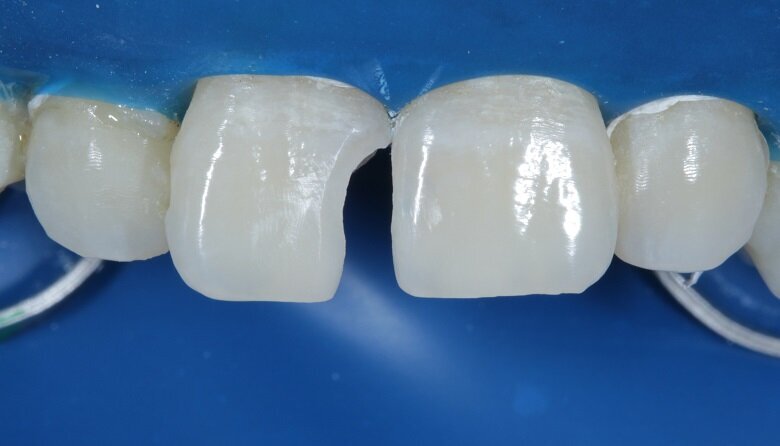

To begin with, the shade (hue) was evaluated using the button technique before isolation. Small balls of different shades of composite (dentin, body and enamel) were placed on the tooth and cured (Fig 4). Value is another important factor which needs to be considered while shade matching.

Fig 4: Shade Evaluation : Button technique (Hue)